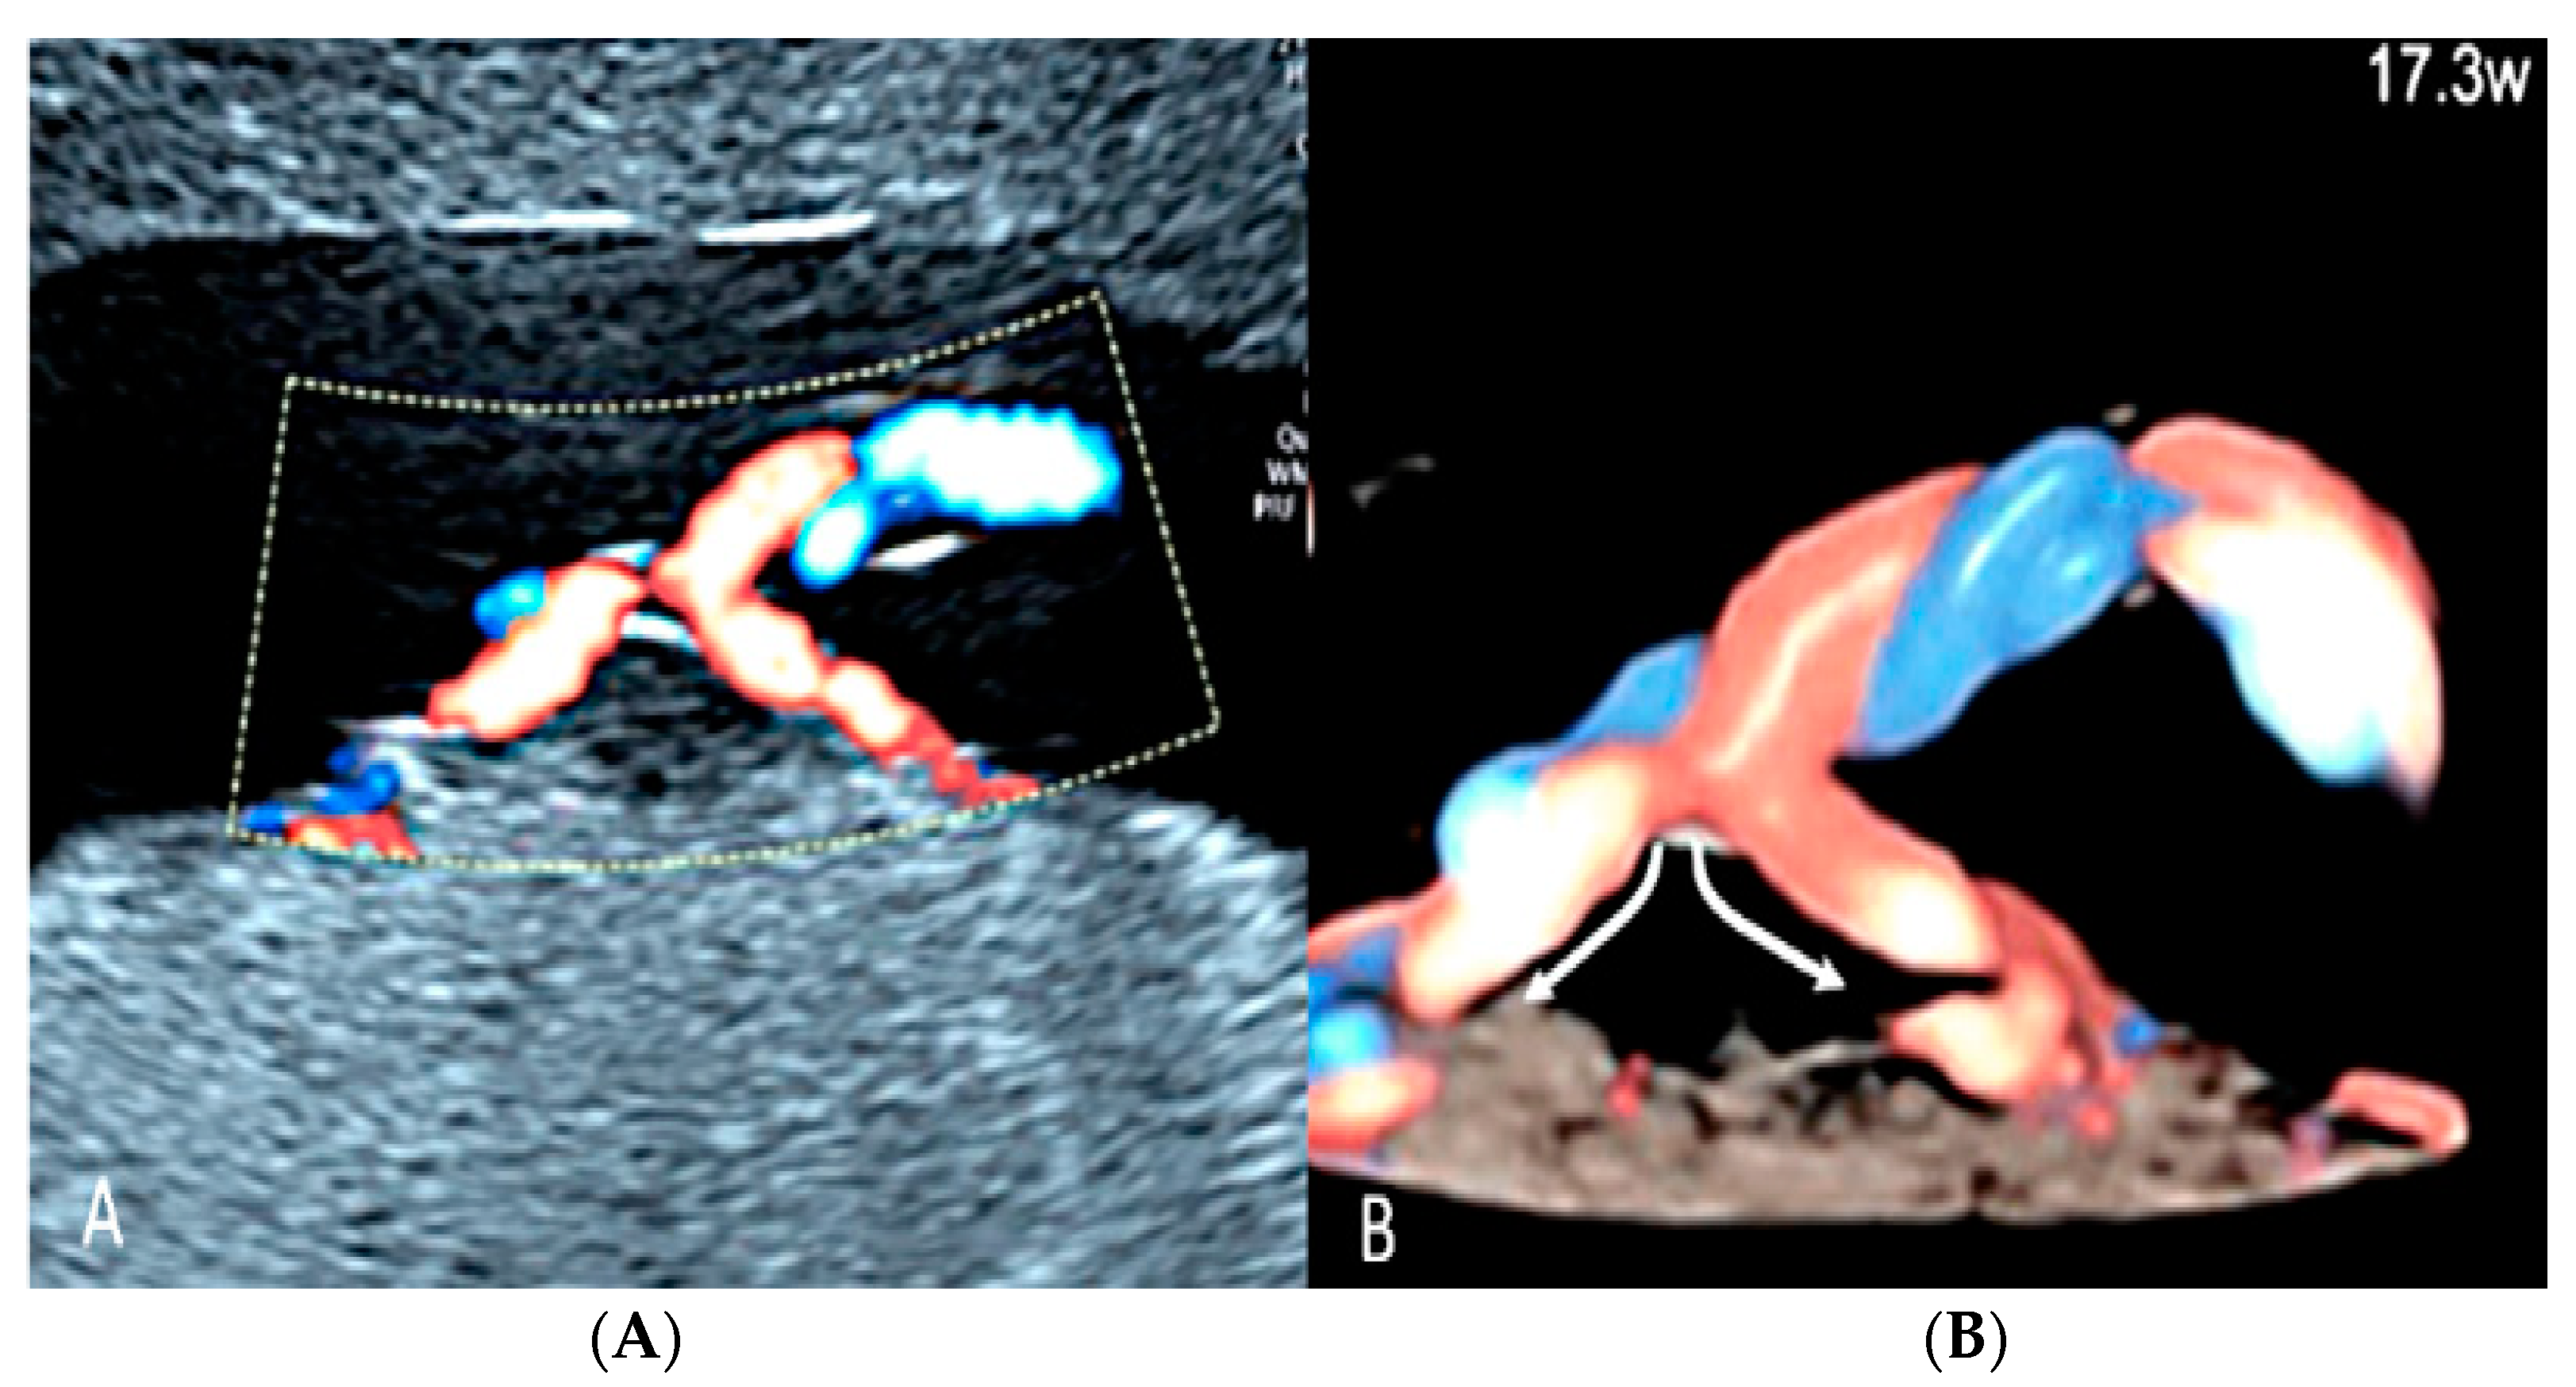

3.2.2. Vasa Praevia

3.2.3. Velamentous Umbilical Cord Insertion